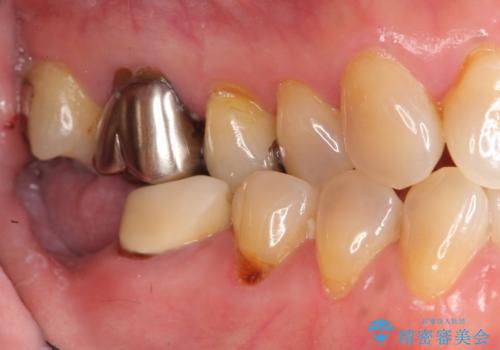

奥歯 インプラントによる機能回復

- 歯を欠損し、噛めないことの治療を希望され来院されました。

インプラントを用いて、しっかりとかめるような治療を計画します。

- 45万円(ストローマンインプラント・骨造成・チタンカスタムアバットメント・ジルコニアクラウン)費用は治療当時の料金となります

最後方臼歯はインプラントを用いることでしっかりと咬合機能を回復することができます。